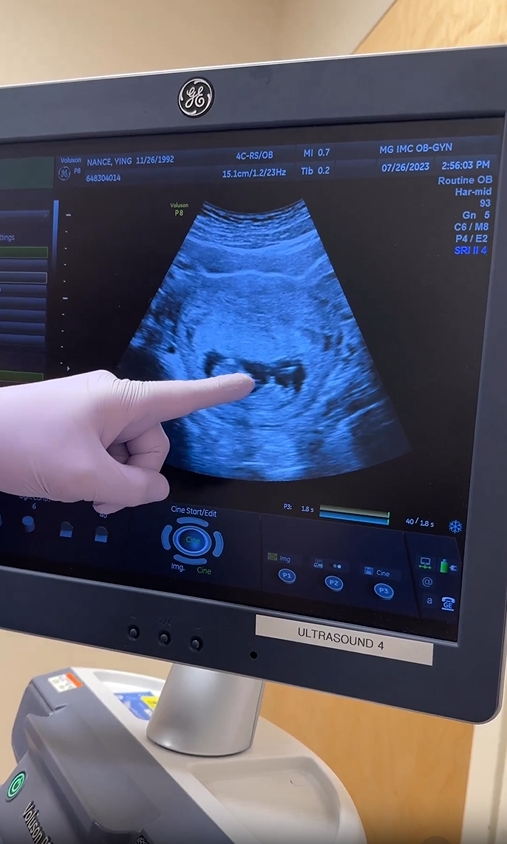

โดย หญิง พลอยชมพู ได้โพสต์คลิปโชว์ภาพอัลตราซาวด์ในครรภ์ พร้อมระบุแคปชั่นว่า “กว่าจะได้เจอหมอ ท้องจนลืมไปเเล้วว่าท้อง Baby #2 coming Feb 2024! Lizzie’s going to be a big sissy” (ลูกคนที่ 2 จะคลอดเดือนกุมภาพันธ์ 2024 น้องลิซซี่กำลังจะกลายเป็นพี่สาวแล้ว)